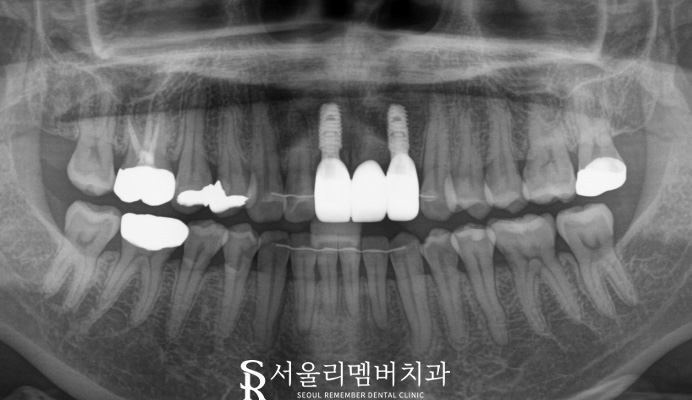

가이드를 통해

식립을 진행해 주었습니다.

빠른 회복 시간으로 골 유착까지 잘 되었는데요.

신림역 치과 자체기공실에서 제작한

보철까지 수복해 주면서 마무리 하였습니다.

치료기간 24. 02. 07 ~ 24. 07. 12